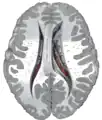

This is a transverse view of the caudate nucleus from a structural MR image.

Transverse view of the caudate nucleus from a structural MR image

The head and body of the caudate nucleus form part of the floor of the anterior horn of the lateral ventricle. After the body travels briefly towards the back of the head, the tail curves back toward the anterior, forming the roof of the inferior horn of the lateral ventricle. This means that a coronal (on a plane parallel to the face) section that cuts through the tail will also cross the body and head of the caudate nucleus.